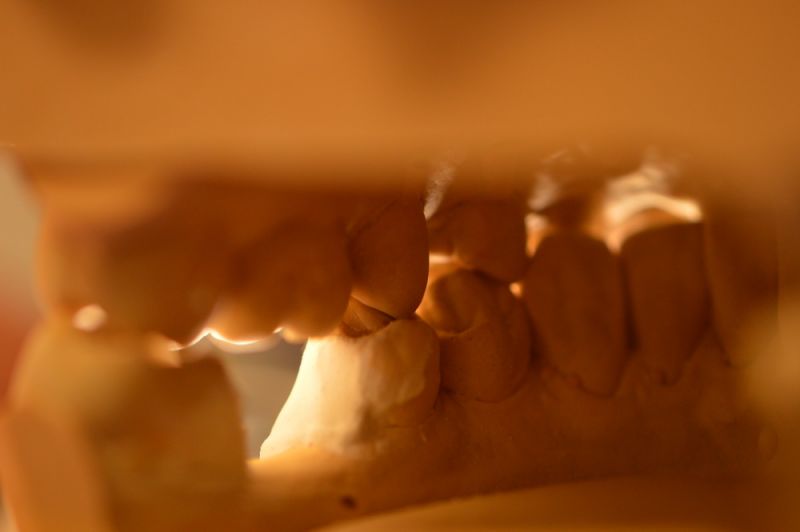

Es läuft dfas Nachweisverfahren einer CMD unter Einsatz eines adjustierten Aufbissbehelfs.

Deutlich erkennbar die Nonokklusion in neuromuskulär zenmtrierter Bisslage